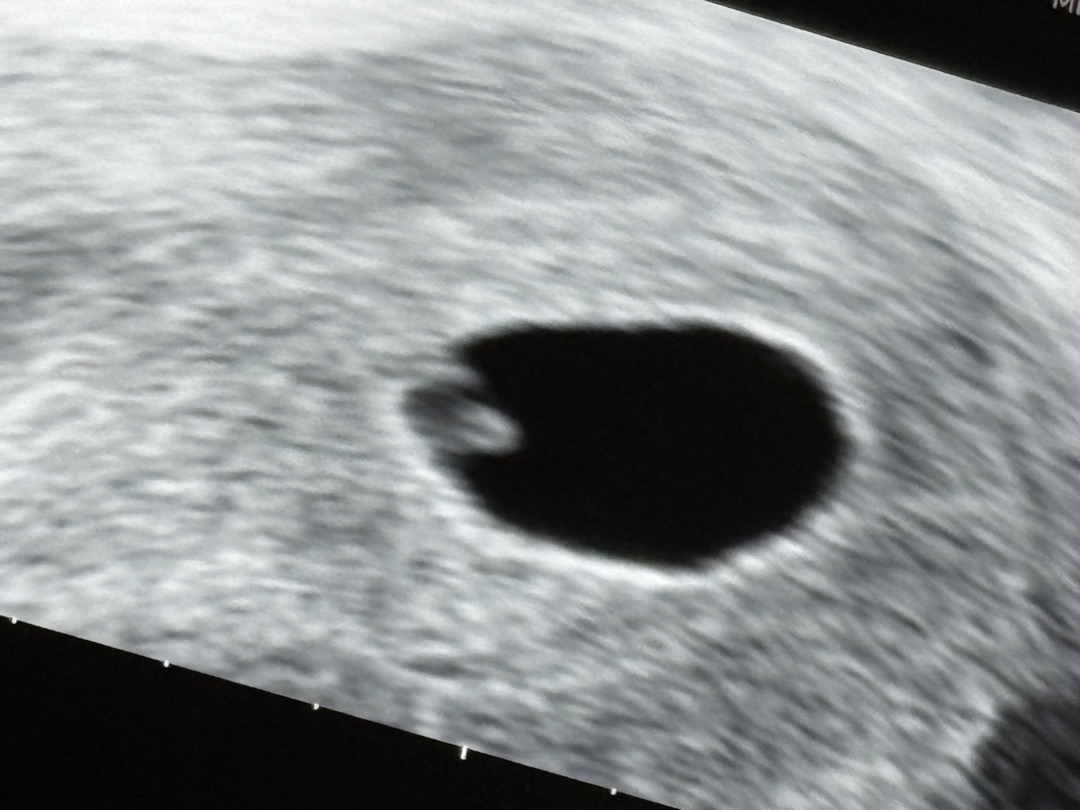

6주1일차

오늘 난황이랑 심장반짝이는거 보고 왔어요:) 다른분들은 다이아반지가 아주 잘보이던데 저는 2mm밖에 안되는 아가알맹이가 강낭콩모양으로 시선강탈해버려서ㅋㅋㅋᩚㅋᩚㅋᩚ 링이 잘 안보이네요 옆으로 넘어진 다이아반지에 심장소리도 들어보려했지만 아직 깨끗하게 안들려서 다음주에 듣기로했어용ㅎㅎㅎ 그래도 잘크고 있다하니 입덧 심해도 이겨지네요ㅠ